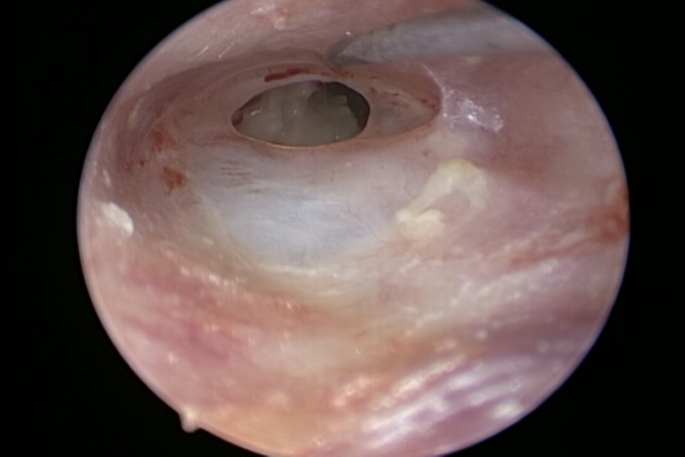

Results: The study included 51 patients who had endoscopic tympanoplasty. The mean age was (33.65 ± 10.840) years. The study showed no statistically significant difference between the preoperative and postoperative bone conduction threshold. In addition, Pearson correlation test showed no statistical association between the total endoscopic usage time and the postoperative bone conduction threshold. No significant vertigo nor facial nerve affection were observed in the postoperative period.

Conclusion: Endoscopic tympanoplasty as an example of EES does not affect the inner ear structures, clinically described as it does not affect the postoperative sensorineural hearing, facial nerve function nor the balance.